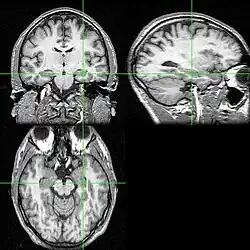

Bylo prokázáno, že řidičům londýnské taxi služby se při jízdě a vyhledávání tras aktivuje příslušná část hipokampu během výběru příslušné trasy a dochází k jeho fyziologickým změnám. Funkční magnetická rezonance (fMRI) odhalila, že hipokampus řidičů byl aktivní tehdy, když taxikáři poprvé plánovali cestu nebo když museli zcela změnit cíl během jízdy.[2][3]